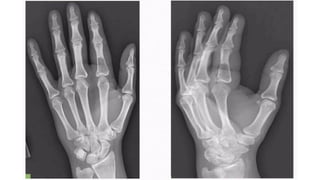

Chondroma/Enchondroma

• • 50% in hands - commonly in phalanges, less commonly in metacarpals

• Cartilaginous tissue is not radiopaque

• • Radiolucent lesion

• Expansion and thinning of overlying cortex

• No periosteal reaction in the absence of fracture

• Z o n e o f t r a n s i t i o n is n a r r o w a n d s c l e r o t i c

• Endosteal scalloping +

• Flecks o f c a l c i fi c a t i o n w i t h i n t h e lesion

• usually purely lytic in phalanges, in other

• locations, enchondromas are expansile, with

• characteristic "rings and arcs" calcifications.

Plain radiograph & CT scan features